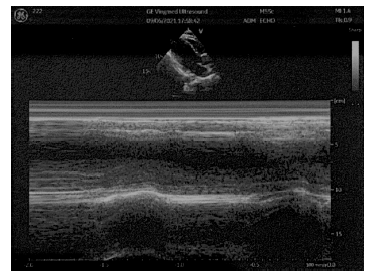

甲狀腺超聲:甲狀腺瀰漫性、對稱性腫大。彩色多普勒血流成像(CDFI):

甲狀腺血流增多。